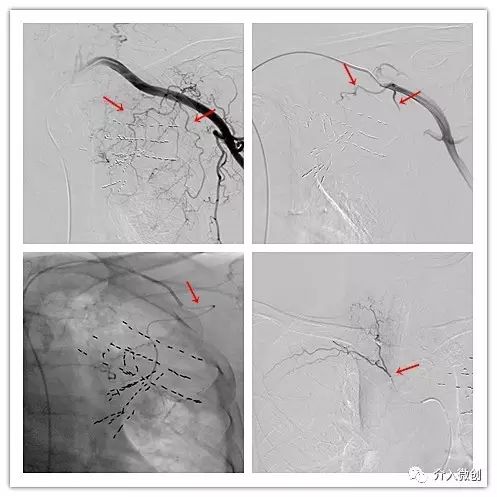

DSA下行支气管动脉化疗栓塞术+留置导管持续化疗灌注术,进一步控制双肺转移病灶